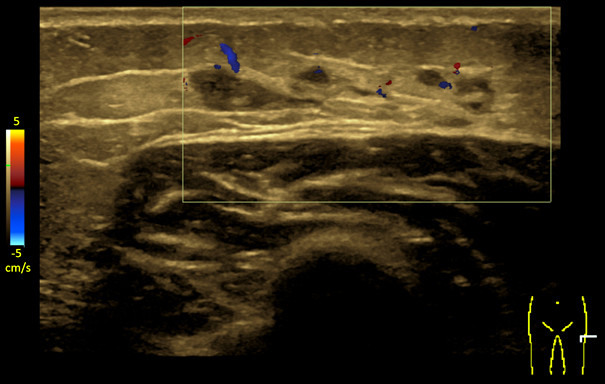

En ultralydundersøkelse tre måneder etter at kulen ble oppdaget, viste en skarpt avgrenset, uregelmessig lobulær, multilokulær cystisk/anekkoisk lesjon (ca. 3 × 0,5 cm) i subkutant fettvev, uten affeksjon av muskelfascien. Differensialdiagnoser var organisert hematom, sekvele etter en fokal inflammatorisk prosess, vaskulær malformasjon eller annet (figur 2). Kontroller tre og ni måneder senere viste uendret lesjon. Radiologen anbefalte vurdering av barnelege.